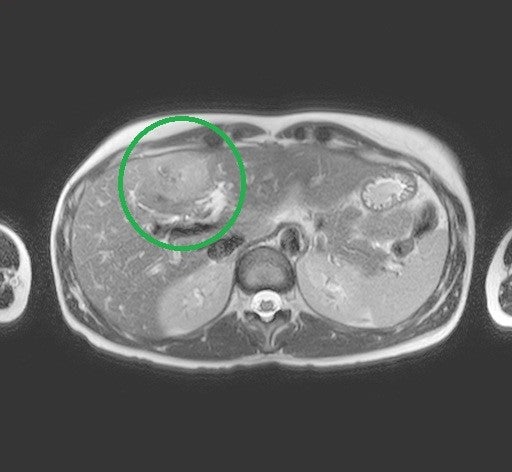

3-4/2025 CT staging – susp. cholangiokarcinom v terénu PSC s lymfadenopatií

Obr. 2: Stejné ložisko v CT obraze